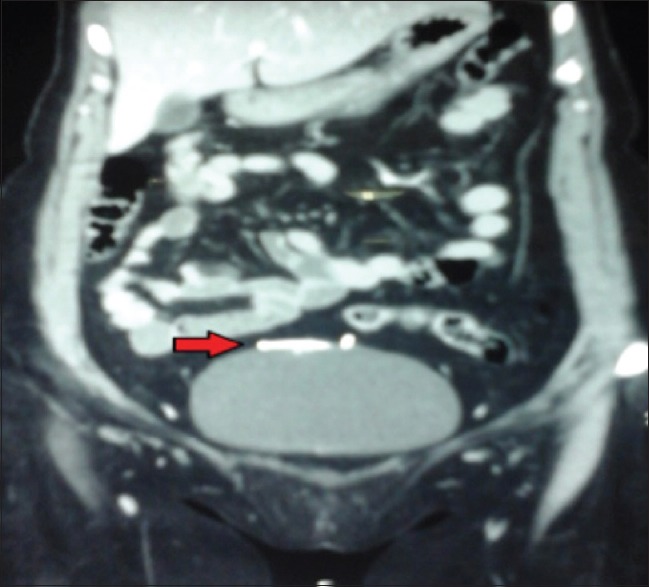

最常用的长期可逆女性避孕方法是宫内节育器(IUCD)。然而,它的使用与文献记载的并发症有关。子宫穿孔,虽然罕见,但可以说是所有这些并发症中最重要的手术。我们报告一例48岁的4+0(4活着)妇女,17年前植入了IUCD,此后有两个孩子,却忘记了她有这个装置。随后,宫内节育器经膀胱穹窿移位至腹膜腔,膀胱内宫内节育器尾线周围形成结石,引起反复尿路感染。这种“衣领钉”效应使得单独的膀胱镜或腹腔镜手术不成功,需要联合手术。本病例报告强调需要联合腹腔镜和膀胱镜的方法在检索的不寻常的表现易位宫内节育器。

The most commonly used long-term reversible female contraception is intrauterine contraceptive device (IUCD). Its use is however associated with documented complications. Uterine perforation, though rare, is arguably the most surgically important of all these complications. We report a case of a 48-year-old para 4+0 (4 alive) woman who had IUCD insertion 17 years earlier and had forgotten she had the device having had two children thereafter. The IUCD was subsequently translocated through the dome of the bladder into the peritoneal cavity with calculus formation around the tail and thread of the IUCD in the urinary bladder causing recurrent urinary tract infection. This "Collar Stud" effect made either cystoscopic or laparoscopic retrieval alone unsuccessful necessitating a combined approach. This case report highlights the need for a combined laparoscopic and cystoscopic approach in the retrieval of the unusual presentation of translocated IUCD.